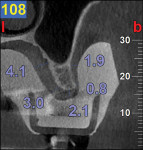

A CBCT study shows hard tissues and the shadow of soft tissues as long as they are surrounded by hard tissue. The pulpal tissue of the teeth is not visible, but the outline of the pulp chamber is visible. The mandibular nerve is not visible, but the cortical bone surrounding it does appear on the CBCT, making it possible to deduce where the mandibular nerve is expected to be. The proposed visualization technique allows very strong contrast to create a negative, much like the just-discussed image of the mandibular nerve. The concept is rather simple; VPS impression material can be radiopaque, but not all materials are radiopaque to the same extent, and some are not radiopaque at all (Figure 2). The patient wears a VPS impression during the CBCT exposure (Figure 3 and Figure 4). This can be the actual impression, or a dedicated impression made from a diagnostic cast (Figure 5). This simple technique shows a very distinct space, which is visible between the VPS material and the bone (Figure 6 and Figure 7). For the purpose of the 3D Click Guide fabrication, this space would otherwise be measured with the bone-sounding technique, as discussed in Part 1 of this series. Because the surface of the VPS impression visible in the CBCT image is exactly similar to the surface of the cast, the two can be exactly superimposed. Within the CBCT software, simple measurements can be made. Those measurements are made at the same locations as those used when bone sounding. Those measurements are then transferred to the cast. Additional information—eg, location of the mandibular canal—can be extrapolated and drawn as needed (Figure 8 and Figure 9).

An 80-year-old woman, who presented with a missing lower molar, requested an implant-supported replacement. Advanced periodontal bone loss at site No. 19 resulted in considerable resorption of the alveolar ridge after healing. Although simple bone sounding is the preferred data-gathering technique for the author, in this case, there was insufficient information available to safely perform an osteotomy. The decision was made to gather additional information with a CBCT study.

The cast was sectioned 4 mm distal of tooth No. 20. The data from the corresponding cross-sectional cut were transferred to the cast. The ideal buccolingual axis was drawn onto the cast, based on a screw access hole in the central fossa of the future crown. A small hole was drilled at the desired location of the shoulder of the implant. The pin of the Bucco Lingual Positioner (BLP) was placed in the hole, and the central groove of the BLP was lined up with the drawn implant axis. A drop of fast-setting cyano-acrylate glue was applied to lock the BLP in place (Figure 11). The opposing part of the cast was adjusted and the cast was reassembled into the Accu-trac tray. At this point, the buccolingual axis and the top of the implant were irreversibly set, and the mesiodistal could be determined without the risk of making inadvertent changes in the buccolingual plane. The correction slot in the crossbar of the wing assembly fits snugly over the top of the BLP, allowing mesiodistal rotation and mesiodistal translation (Figure 12). Once the correct mesiodistal position was selected, the wings were irreversibly connected to the vacuformed carrier by means of ortho-acrylic (Orthoresin, DENTSPLY International, www.dentsply.com); then the cross-sectional bar was removed, allowing placement of a rotation block. The surgical guide was placed in the mouth and a periapical radiograph was exposed (Figure 13). Note that if the buccal and lingual wings overlap and appear to be one, the radiograph has been taken exactly perpendicular to the ridge, allowing a decision to be made because the image is of acceptable diagnostic quality. In this case, the trajectory was as desired, and the 0º rotation block was selected, as there was no need for rotation adjustments by means of the 3º or 7º rotation blocks (Figure 14). The surgical guide was sterilized in a cold sterilizing solution and the surgery was performed per the manufacturer’s drilling protocol. A 8.5-mm x 4.3-mm implant (NobelActive™ 4.3 x 10 mm, Nobel Biocare, www.nobelbiocare.com) was placed as planned (Figure 15).